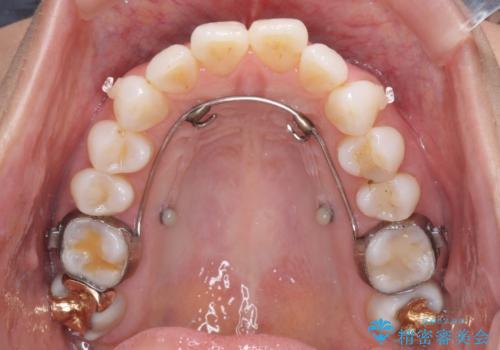

上顎歯列全体を後方に移動させる必要があり、インビザライン単体での治療は困難と判断し、補助装置により左右側方歯列を移動させた後にインビザラインを用いることとしました。

インビザライン単独でも上顎歯列全体を後方移動することで臼歯の咬み合わせを改善できる場合もあります。しかしながら、矯正治療は当初設定したゴールに到達する必要があり、今回のような場合ではインビザライン単独では達成の可能性が低くなるので、補助装置を使用して、より確実に治療を行うこととしています。